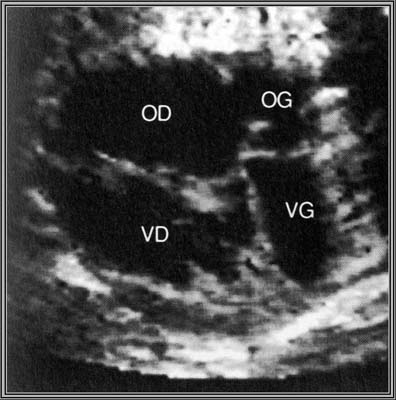

- Large défaut septal concernant à la fois les cloisons inter-auriculaire et inter-ventriculaire

- Valve auriculo-ventriculaire commune qui connecte les deux oreillettes aux ventricules

En diastole, la valve auriculo-ventriculaire commune s’ouvre dans les deux ventricules.

En systole, la croix du cœur n’existe pas, de part la présence d’une CIV du septum d’admission et d’une CIA située au contact de la valve AV commune